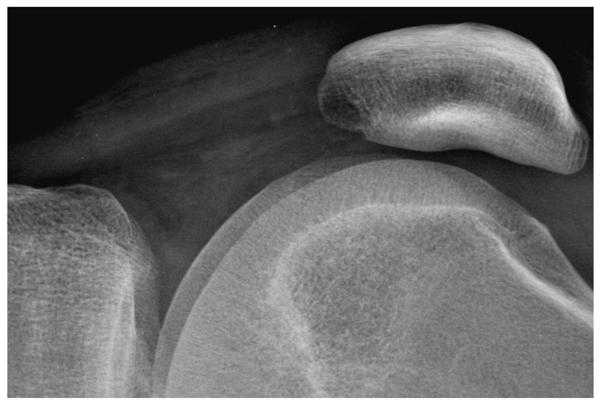

When the edge restoration filter is appropriately specified, fine detail has a realistic appearance and the image will not have excessive noise. This is illustrated in figure 3 for a lateral knee view recorded using a CR system with a high-resolution phosphor screen. Inappropriate specification of the restoration filter can lead to artifacts. In some systems of earlier design, filters were implemented using spatial convolutions based on a small kernel that were not able to amplify image components with low and intermediate spatial frequencies. These were often applied with excessively high gain. This over-amplification of high spatial frequencies causes edge artifacts appearing as an oscillating signal that is sometimes referred to as ‘edge ringing’.

Figure 3a. A digital radiograph of the knee taken with a high resolution CR screen (HR screen, Eastman Kodak Company) is illustrated using display processing with no edge restoration.

Figure 3b. The knee radiograph shown in figure 3a is illustrated using display processing with edge restoration.